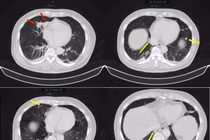

Ngày càng ghi nhận nhiều trường hợp mắc đa ung thư nguyên phát. Phối hợp đa chuyên khoa trong chẩn đoán, điều trị là yếu tố then chốt giúp kiểm soát tốt bệnh.

Các bác sĩ phát hiện người bệnh mắc đồng thời hai bệnh lý gồm ung thư bàng quang và ống mật chủ, trong khi không có triệu chứng rõ ràng.

Bệnh nhân 50 tuổi mắc đồng thời 3 ung thư tiêu hóa hiếm gặp, đã thành công qua ca mổ kéo dài hơn 13 giờ, mở ra hy vọng điều trị hiệu quả.